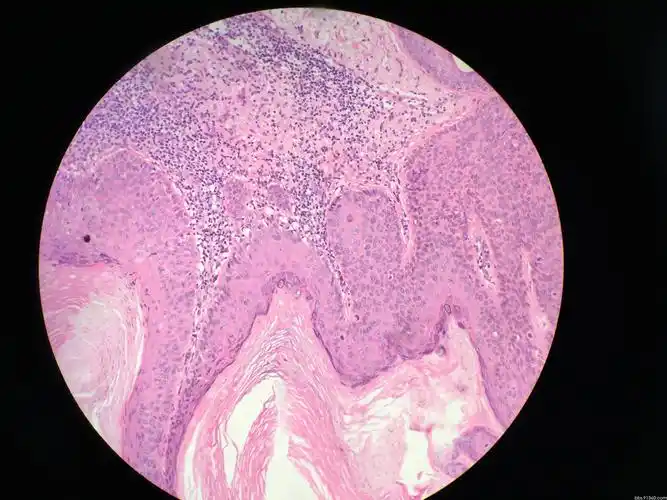

面部皮肤斑块 - 皮肤病理 - 91360病理论坛

真实的皮肤病理切片

3分钟皮肤病理系列-001 寻常疣

左足背肿物 - 皮肤病理 - 91360病理论坛

面部皮肤结节 - 皮肤病理 - 91360病理论坛

50个常见皮肤病的典型病理表现(图文版)

手背皮肤溃疡 - 皮肤病理 - 91360病理论坛